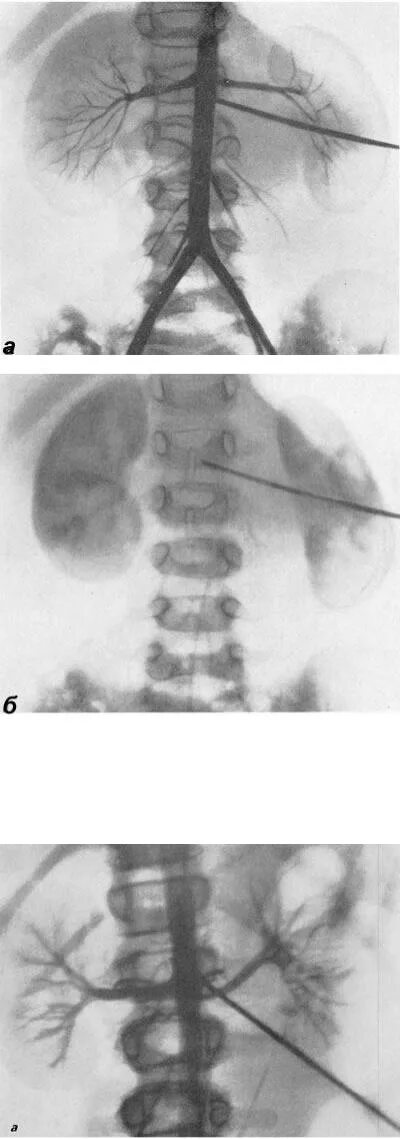

Нефроптоз 2 степени что это